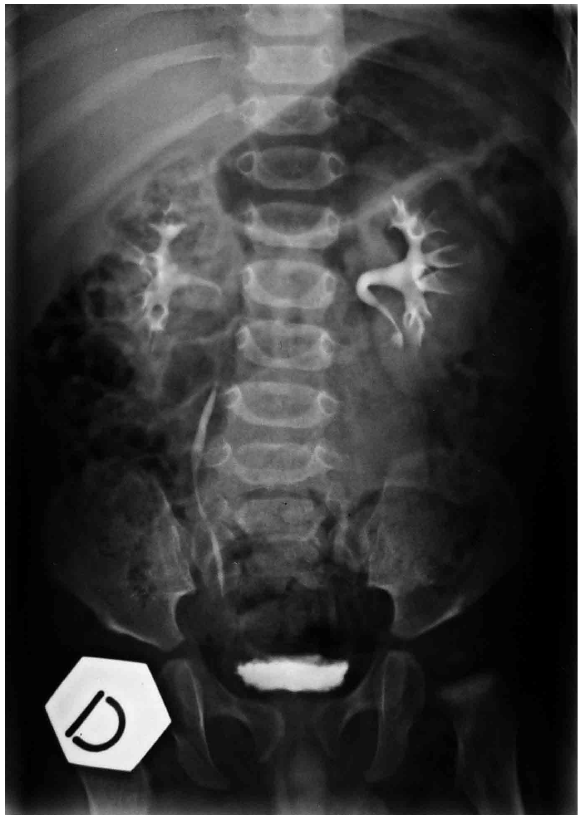

Complete objective response of neuroblastoma to biological treatment.